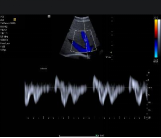

eSie Measure 一键自动测量 :快速自动测量心脏的 2D/M/PW 图像,其良好的一致性、重复性、和准确性,降低了手动测量的误差。可测量的参数包括:

‒ 2D:左房、左室、室间隔、室壁径线 EF、FS等

‒ M:主动脉、左房、左室、室间隔、室壁径线 EF.FS 等

‒ Doppler:四个瓣口的血流峰值流速、时间速度积分、减速时间、跨瓣压差、平均压差、E/A、返流流速、压差等